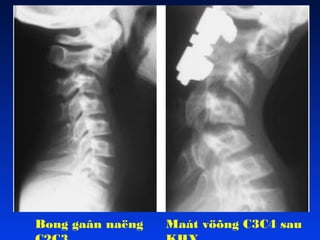

GAÕY TRAÄT C5C6LUÙC SANH, LIEÄT TÖÙ CHI

Bong gaân naëng Maátvöõng C3C4 sau